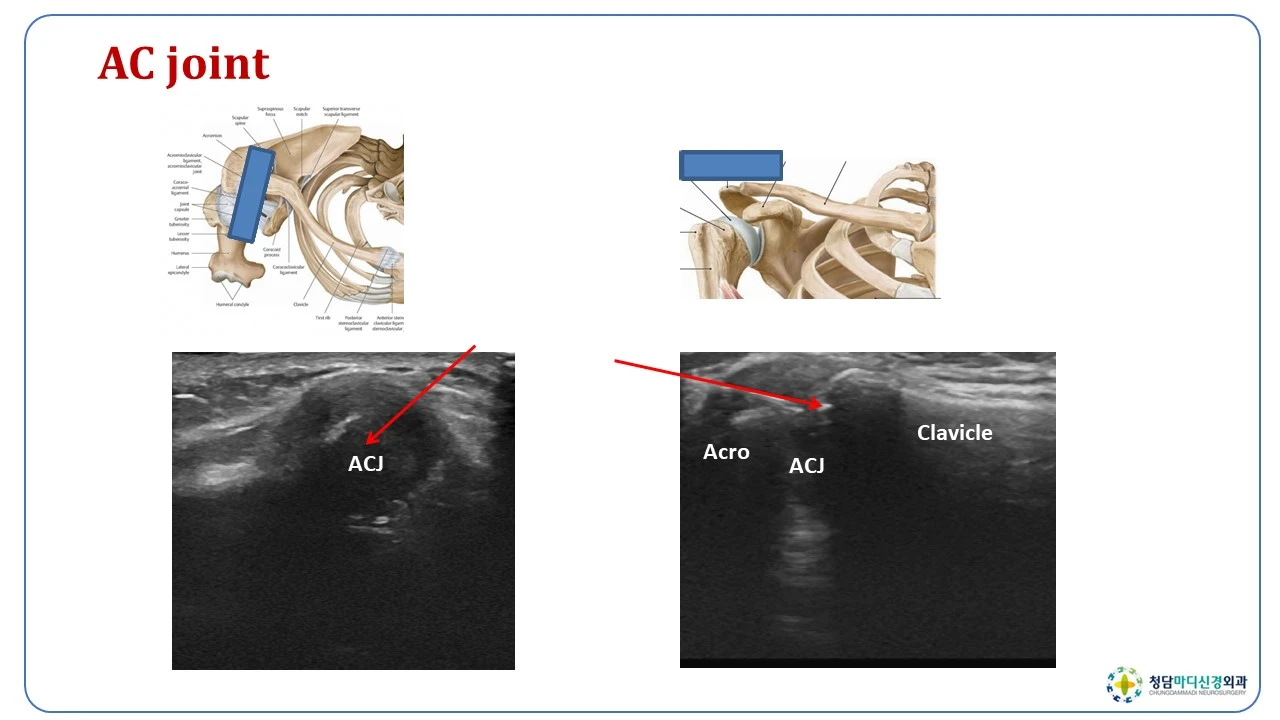

견쇄관절은 어깨의 상단에 있는 견봉과 쇄골이 만나서 이루는 관절인데요, 관절 연골의 퇴행성 변화나 외상에 의하여 염좌 등이 쉽게 발생하는 곳입니다. 어깨관절의 통증 중에서 약10% 정도를 차지하는 흔한 질환입니다.

견쇄관절을 지지하는 구조는 관절낭인대로 견쇄인대가 관절부를 둘러싸고 있으며, 그 외부를 오구쇄골인대와 오구견봉인대가 지지를 해서 안정성을 주고 있습니다.

견쇄관절의 프롤로치료를 할 때에는, 견쇄관절의 해부학적인 모양을 정확하게 아는 것이 중요합니다. 이 관절은 견봉보다 쇄골이 약간 더 높은 위치에 있으며, 우측은 11시 방향, 좌측은 1시 방향으로 열려 있기 때문에, 이 방향에서 바늘을 자입하는 것이 견쇄관절강내로 들어가는 것이 용이합니다. 견쇄관절강 내에 증식제를 주사하고, 상부 견쇄인대와 전면 그리고 후면의 견쇄인대에도 증식제를 주사하면 됩니다.

하부의 견쇄인대에 주사를 정확히 하려면, 초음파투시를 하면서 주사를 하면 쉽고 안전하게 접근을 할 수 있습니다. 최근에는 정확하고 안전한 치료를 위해서 초음파투시를 하는 경우가 많아지고 있습니다.